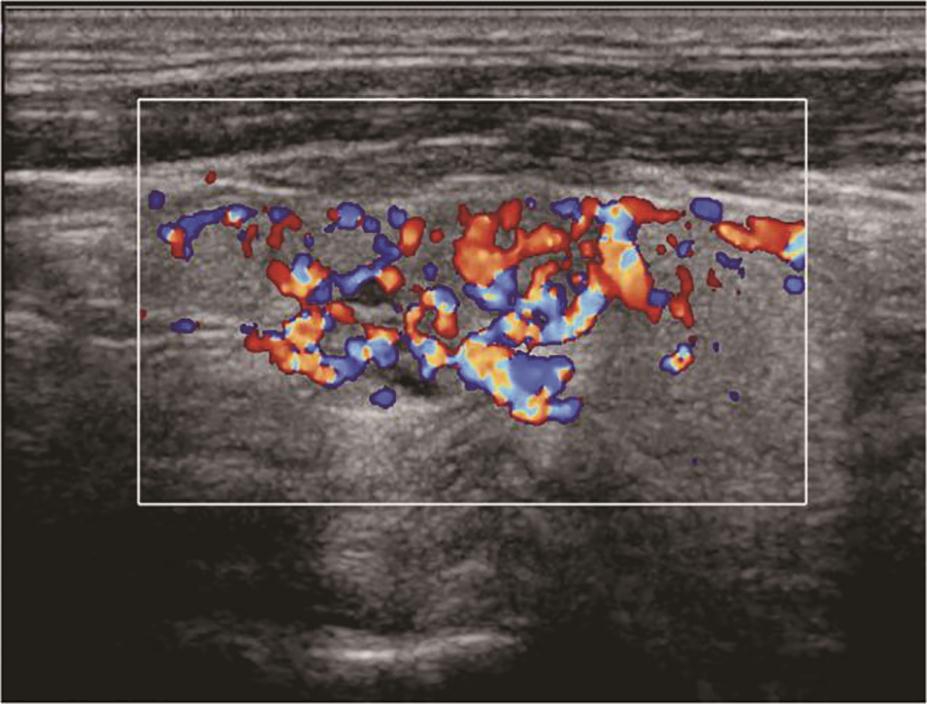

(十一)甲状腺髓样癌

甲状腺髓样癌超声上多为不规则低回声实性结节,内部回声不均,部分病例可伴有囊性成分,髓样癌丰富的血流信号是其超声主要特点。约1/3的髓样癌超声表现不典型,除了血供丰富表现外,类似良性结节(图13、图14)。

:甲状腺左叶中部中低回声内部彩色多普勒血流信号丰富而杂乱.jpg)

图14左侧颈部纵切面(与图3-3-13同患者、同切面):甲状腺左叶中部中低回声内部彩色多普勒血流信号丰富而杂乱